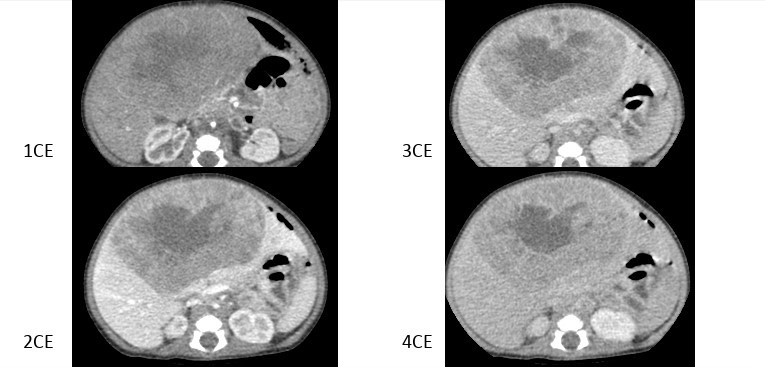

2968. Девочке 2 месяцев выполнена компьютерная томография брюшной полости с контрастным усилением, рентгенологическая картина соответствует